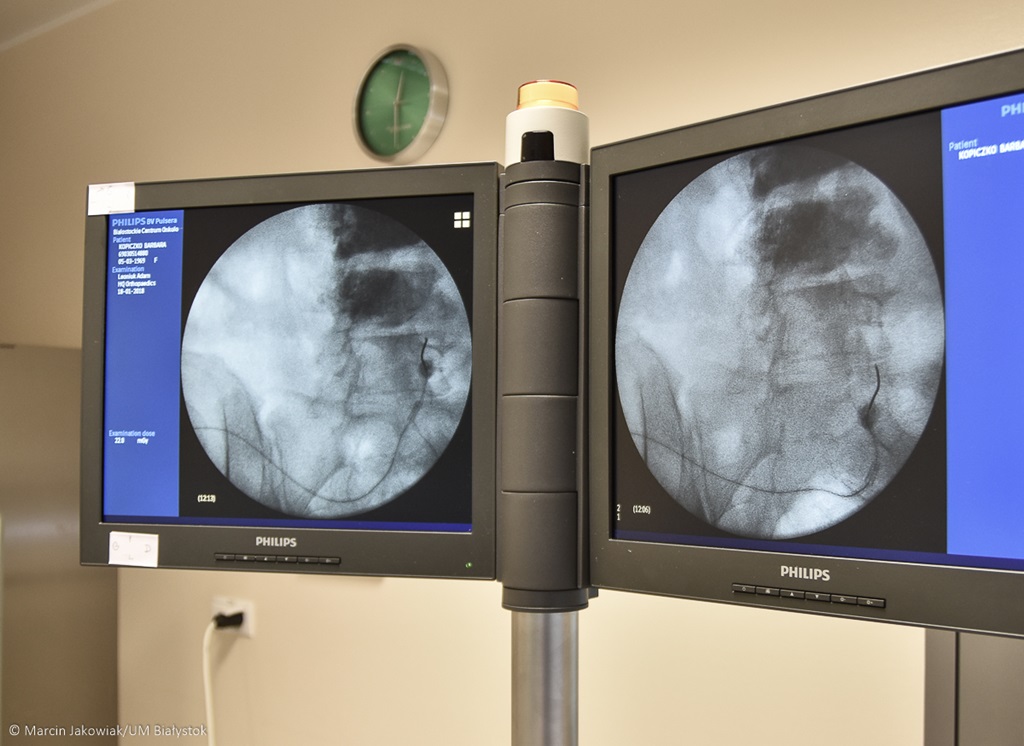

Do niedawna korzystali z nieprzystosowanego stołu zabiegowego, co znacznie ograniczało ich możliwości. Dzięki dotacji z Urzędu Miejskiego w Białymstoku, Białostockie Centrum Onkologii kupiło nowy sprzęt, wykorzystywany do leczenia bólu.

Chodzi o specjalistyczne narzędzia chirurgiczne i nowoczesny stół niezbędny do skutecznego przeprowadzania zabiegu termolezji, czyli sposobu leczenia bólu – mówi lekarz anestezjolog z centrum onkologii Dariusz Kożuchowski.

Zakupiony sprzęt kosztował prawie 200 tys. zł. Zakup sfinansowano z budżetu miasta, choć szpital formalnie podlega marszałkowi województwa. Zależy nam na poprawie jakości leczenia mieszkańców – mówi prezydent Białegostoku Tadeusz Truskolaski.